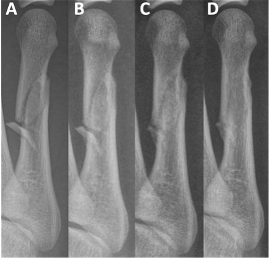

On examination, there was focal tenderness over the dorsal lateral forefoot without gross deformity, open wounds, or sensory deficits. Vascular status was grossly intact. Three views of non-weight-bearing radiographs revealed a mildly comminuted mid-diaphyseal fifth metatarsal fracture with a small angulated butterfly fragment (Figures 1A, 2A, and 3A). On the oblique view there was approximate 3.59mm of gapping noted with 3 distinct fracture fragments. Some shortening of distal metatarsal was apparent as well. The patient was placed in a controlled ankle motion (CAM) boot, provided with crutches, and instructed to remain non-weight-bearing.

One month after the initial injury, swelling and ecchymosis had resolved, and pain was improved. He was able to weight-bear in the CAM boot without difficulty. Follow-up weight-bearing radiographs showed stable alignment with no interval displacement (Figures 1B, 2B, and 3B). We advised him to advance to weight-bearing as tolerated in supportive shoe gear after 2 additional weeks.

At the 4 month mark, weight-bearing radiographs demonstrated osseous bridging across the fracture site (Figures 1C, 2C, and 3C). By 11 months, the patient was pain-free and had returned to full activity. Non-weight-bearing radiographs confirmed complete fracture union with preserved joint spaces and no deformity (Figures 1D, 2D, and 3D). At 16 months, he remained asymptomatic with normal activities of daily living.